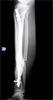

Progress